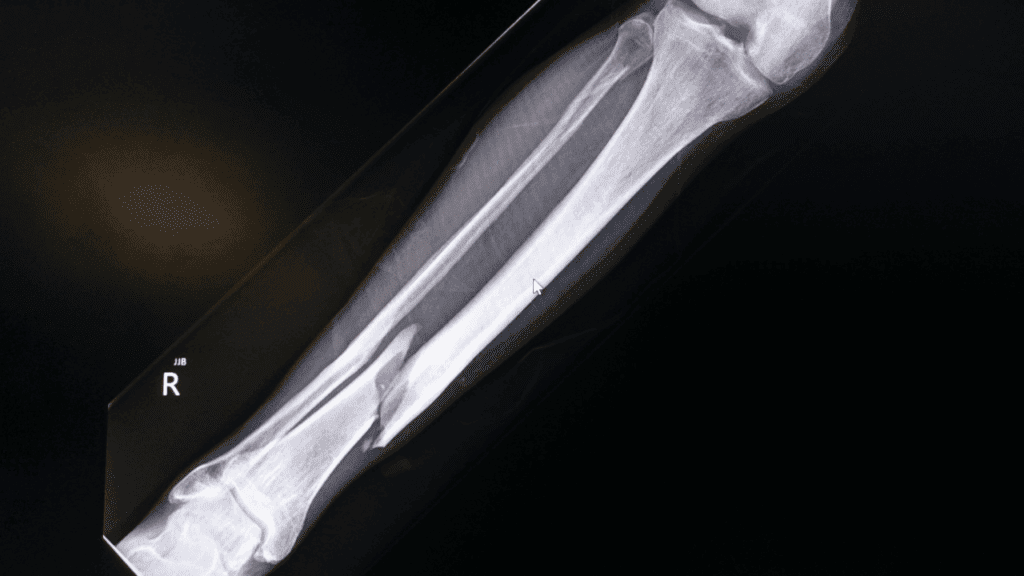

骨肉瘤是最常見的惡性骨腫瘤。由於這種病態的骨骼十分脆弱,加上腫瘤的生長會侵犯原本正常的骨骼結構,因此非常容易發生骨折。

病患可能會因為輕微的碰撞、日常活動,就突然發生骨折。

骨肉瘤可發生在身上的任何骨骼,最常發生在四肢,因為這些部位是骨骼生長最快速的地方。

根據文獻統計,最常見的發病部位依序為:

- 股骨(大腿骨):約佔 42%

- 脛骨(小腿骨):約佔 19%

- 肱骨(上臂骨,靠近肩膀):約佔 10%

症狀 3|骨折

- 結構脆弱:癌細胞生成的不健康骨質取代了健康骨質,導致骨骼較脆弱

- 容易斷裂:無明顯外傷,或只是日常走動、輕微碰撞的情況下發生骨折

- 突然失能:骨折發生時會伴隨劇烈疼痛與肢體變形,導致患者瞬間喪失活動能力